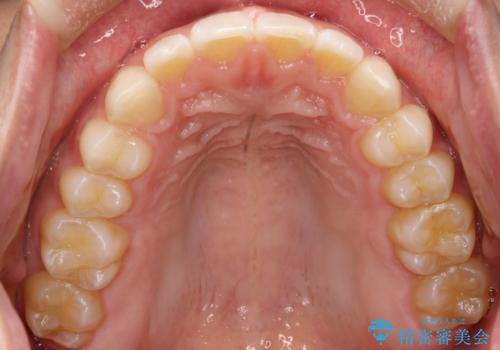

前歯の隙間がきになる インビザラインですきっ歯の治療

インビザラインにて矯正治療を行いました。

しっかり使っていただけたので、スムーズに治療を終了することができました。